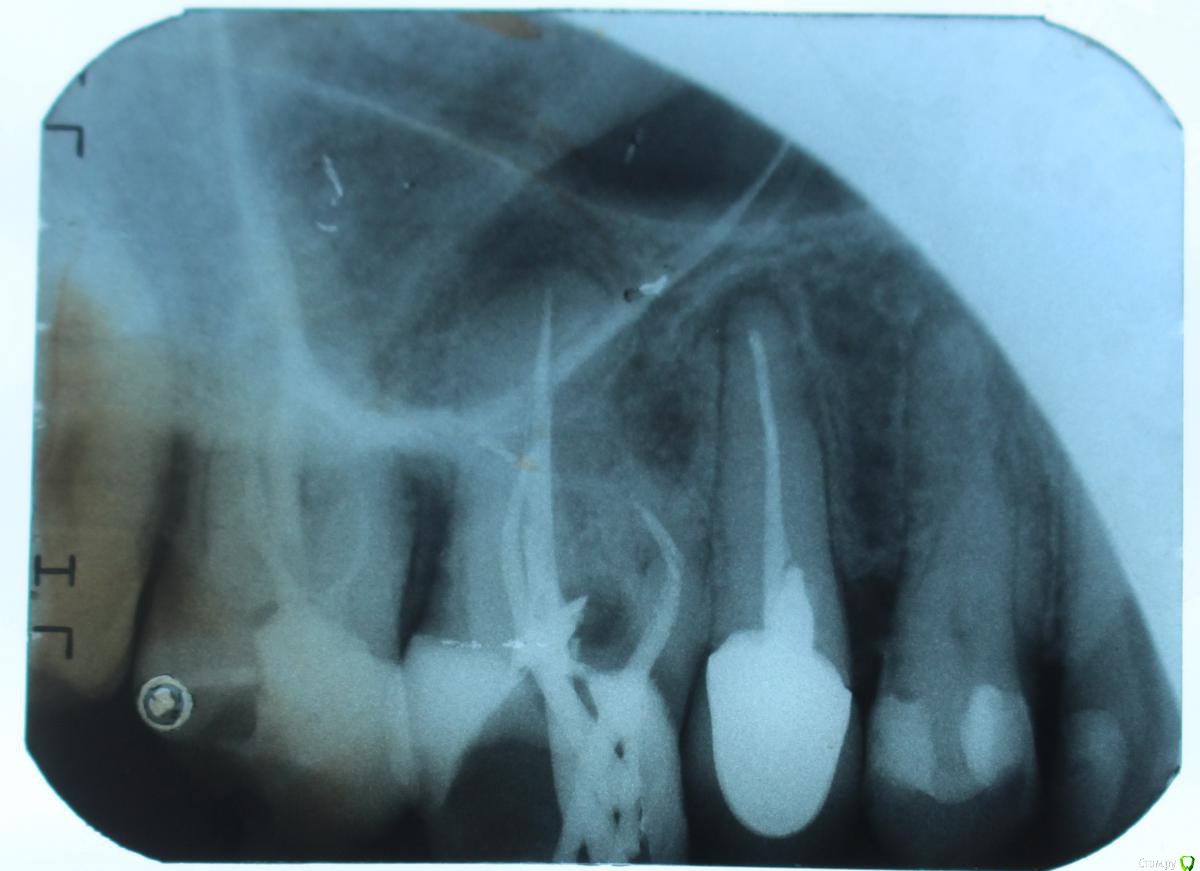

стихия Опубликовано 3 июля, 2017 Поделиться Опубликовано 3 июля, 2017 Здравствуйте, уважаемые стоматологи! Очень прошу вашей помощи. Ситуация такая: год назад пломбировали мне каналы в 26-м зубе. Через пол-года начала чувствовать десну и щеку, сам зуб не болел. Пошла к врачу, сделали снимки, сказал гранулема на 25(про 26-й ничего не сказал), можно наблюдать, если воспалится - сделать резекцию верхушки корня. На прошлой неделе вспухла немного щека и заложило гайморовую пазуху. Опять сделали снимок и сказали удалять 26, спасти зуб нельзя, а в 25 лечить кисту. Я в шоке. Удалять не хотелось бы. Очень прошу посмотреть мои снимки и дать совет: можно ли вылечить кисту 26-го без удаления? Сейчас опухоль спала и зуб практически не беспокоит. Что будет, если вообще его пока не трогать? Выкладываю снимки, сделанные: 1. год назад 2. пол-года назад 3. на прошлой неделе.1. http://s015.radikal.ru/i330/1707/e8/be0d848983dd.jpg2. http://s018.radikal.ru/i508/1707/f4/68ec5e31521b.jpg3. http://s019.radikal.ru/i608/1707/17/603d3bfcc4b7.jpg Ссылка на комментарий

DmitrySH Опубликовано 3 июля, 2017 Поделиться Опубликовано 3 июля, 2017 Здравствуйте!У вас гранулемы на трех зубах, еще седьмой. Все три зуба требуют лечения. Успех лечения не 100%, но шансы есть. В ходе лечения может выявится что-то, из-за чего потребуется удаление. Ищите грамотного эндодонтиста. Ссылка на комментарий

стихия Опубликовано 4 июля, 2017 Автор Поделиться Опубликовано 4 июля, 2017 Начала сегодня лечение. Сняли вкладку и коронку с 25 зуба, вроде все удачно. А вот с каналом произошел неприятный сюрприз - распломбировать его не удалось. Зуб был залечан 15 лет назад, видать каким-то материалом вроде цемента (так сказал врач). Заложил лек-во в канал, которое растворит цемент, если получится, и дальше будем пробовать проходить канал. Если канал не пройдем, будем делать резекцию верхушки и тогда получается зря снимали коронку А насчет 26-го: по-прежднему настаивает на удалении, говорит нет смысла даже пробовать лечить. Говорит, зуб выдвинулся (снизу 14 лет не было антагониста), корни сильно оголились и немного уже пошатывается. Была еще сегодня у одного врача. Она предлагает в 26-м попробовать распломбировать только медиальный канал (который рядом с 25) и заложить пасту лечебную. Говорит, что гранулема в основном около медиального корня, может достаточно будет только его пролечить. Что скажете про такой вариант лечения 26-го зуба? Ссылка на комментарий

DmitrySH Опубликовано 6 июля, 2017 Поделиться Опубликовано 6 июля, 2017 . Вот вы, Дмитрий, пишете, что для вас это ежедневная работа. Т.е. вы такие зубы лечите? Не отправляете сразу на удаление? И насколько успешно? Конечно лечим. очень успешно. На снимках не вижу поводов для удаления. Если в ходе лечения выявляется что зуб невозможно вылечить, то удаляем. Ссылка на комментарий